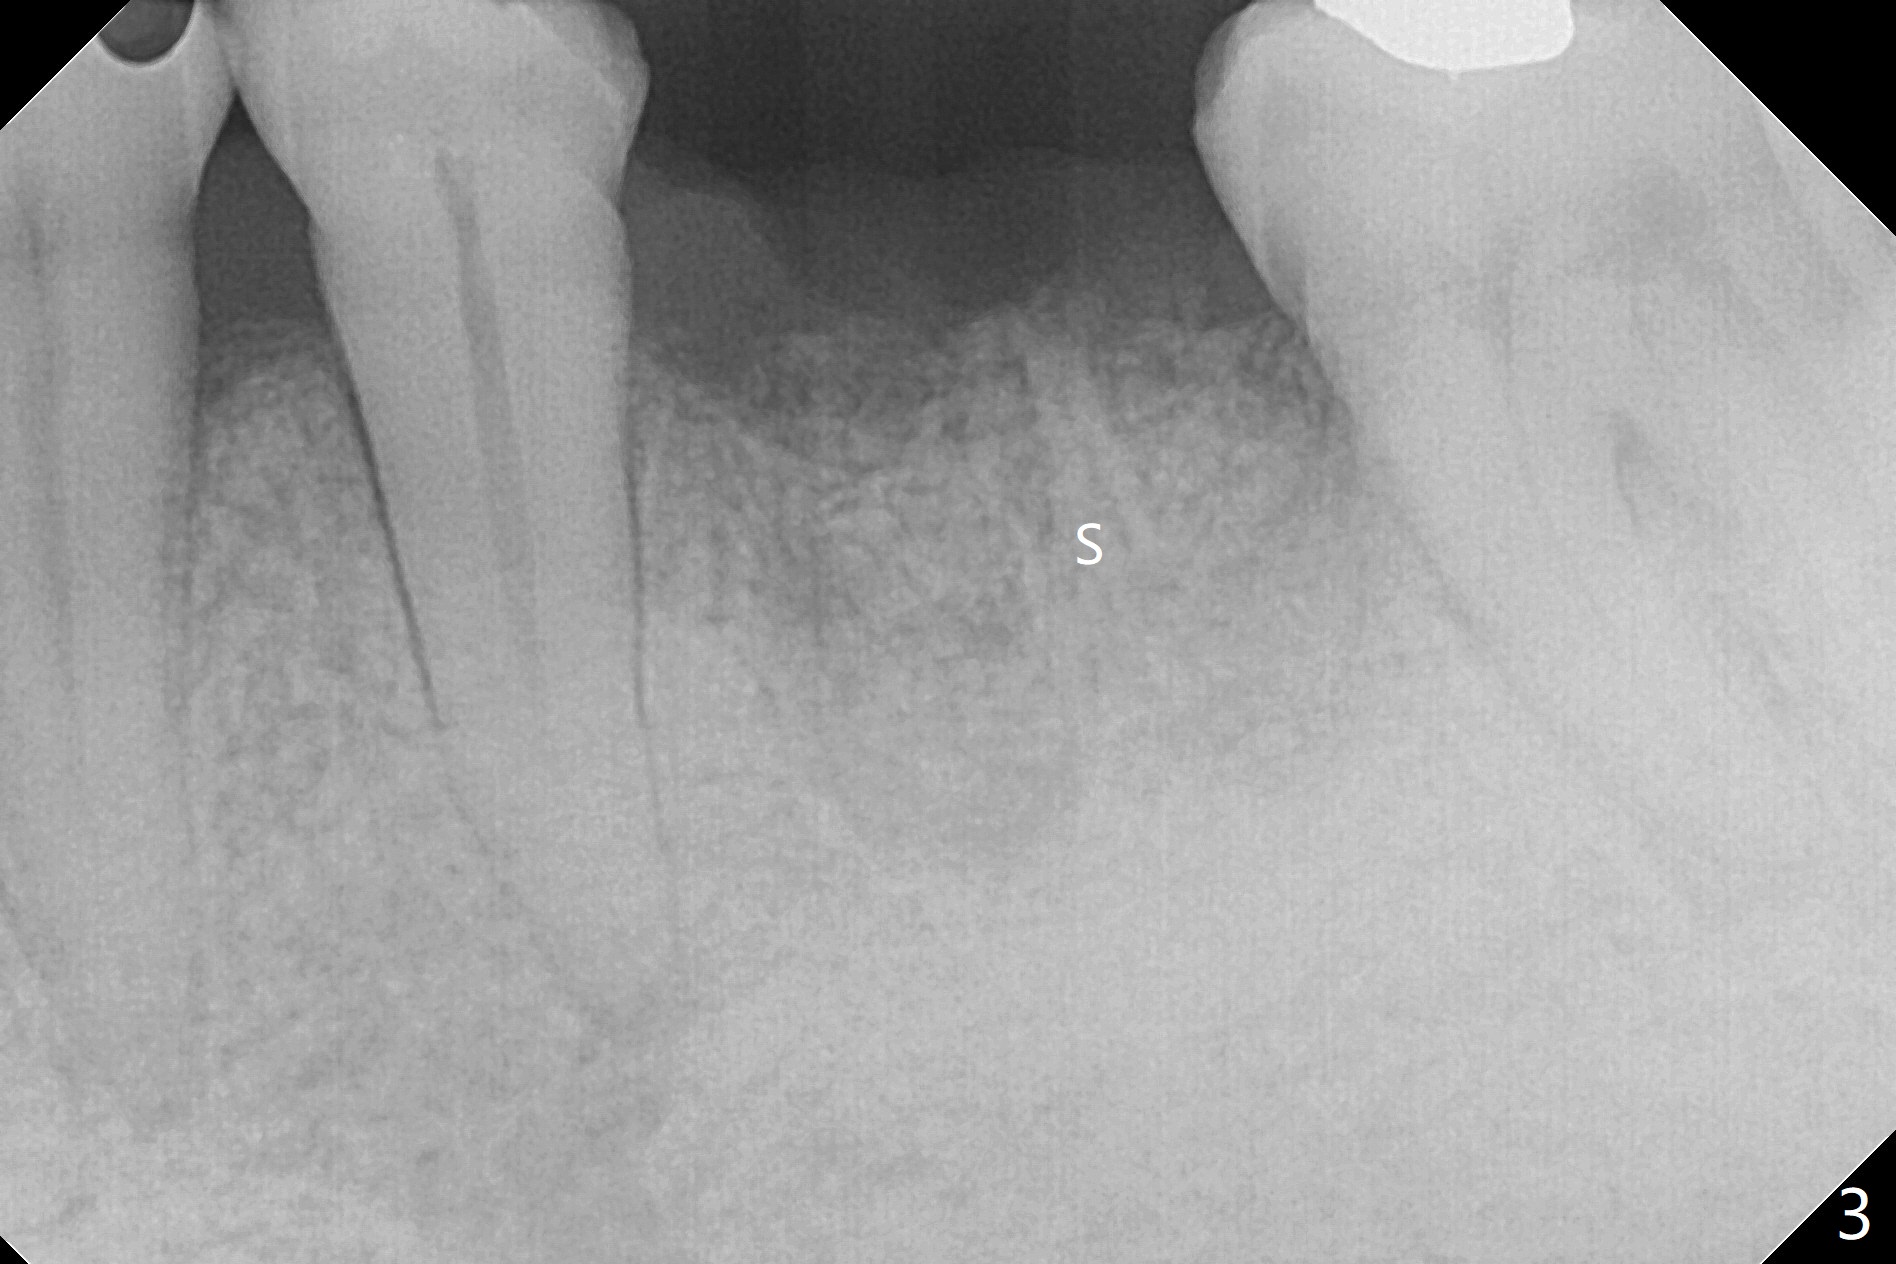

A 73-year-old man (with history of lung cancer with chemotherapy 6 years ago) requests removing the tooth #19 (Fig.1) with the loose mesiolingual fragment (Fig.2 ML). The mesiobuccal plate is low when the tooth is extracted. The septum should provide additional blood supply to bone graft to facilitate healing (Fig.3 S, as compared to the case without it). After placement of 6-month membrane and suturing, acrylic dressing is applied, which is stable 9 days postop (Fig.4 A). The acrylic dressing remains in place 1 month postop (Fig.5). After wiggling, it dislodges fairly easily. The socket heals with slight atrophy (Fig.6).